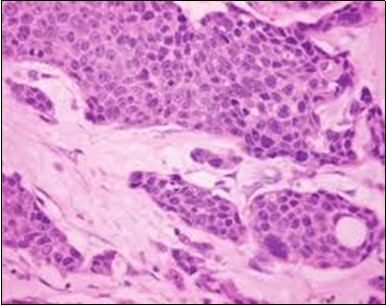

Figure 3.Cohesive accumulations with numerous ductular articulations of carcinoma cells in eccrine porocarcinoma (15).

Cohesive accumulations with numerous ductular articulations                    of carcinoma cells in eccrine              porocarcinoma (15).